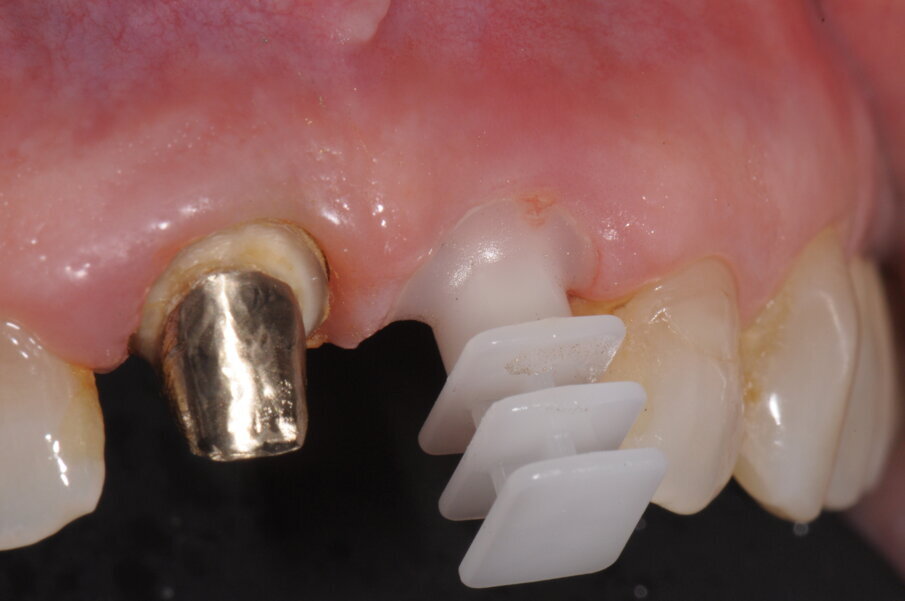

Avendo scelto inizialmente di voler sostituire anche la corona protesica dell’incisivo controlaterale, al termine del posizionamento implantare abbiamo posizionato un coping di protezione sul moncone che è stato poi utilizzato per collegarlo al provvisorio realizzato (Fig. 9). Il provvisorio è stato realizzato secondo tecnica CAD/CAM nella medesima seduta posizionandolo su entrambi gli elementi. Abbiamo preferito supportare il carico dell’impianto unendo le due corone provvisorie eseguite in telio, allo scopo di garantire maggior resistenza, estetica ma soprattutto per una miglior rifinitura dei margini cervicali. Dopo 3 mesi è stato eseguito nuovo controllo radiografico e clinico rimuovendo il provvisorio. Allo scopo di trasferire all’odontotecnico l’anatomia del tragitto transmucoso è stato aggiunto del composito flou al transfer dedicato all’impronta che nello specifico è solo disponibile nella versione di impronta a strappo (Fig. 11), contemporaneamente abbiamo rilevato anche l’impronta del dente adiacente (Fig. 12). Entrambe le corone sono state realizzate con un core in zirconia sviluppata secondo tecnica CAD/CAM e stratificate in ceramica (Fig. 13). Alla prova delle corone valutiamo gli svincoli occlusali oltre ai movimenti parafunzionali, ricordando che la frattura dell’elemento oggetto di impianto è stato causata durante una funzione masticatoria, indice di un sovraccarico funzionale.

Fig. 9 - Posizionamento di una coppetta in resina come base d’appoggio per la ribasatura del provvisorio.

Fig. 10 - I due incisivi centrali sono stati uniti in un unico provvisorio, così da ripartire l’impatto occlusale sull’impianto.